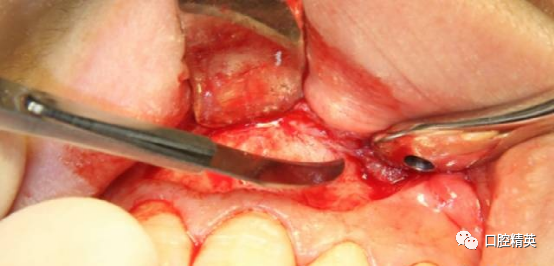

术前检查已知唇侧骨开窗,囊壁与软组织瓣会出现粘连,采用锐性分离,轻柔分开组织瓣并彻底清理瓣内侧。

初步分离后可见较厚的囊壁暴露,夹持后分离囊壁与骨面,争取完整分离。